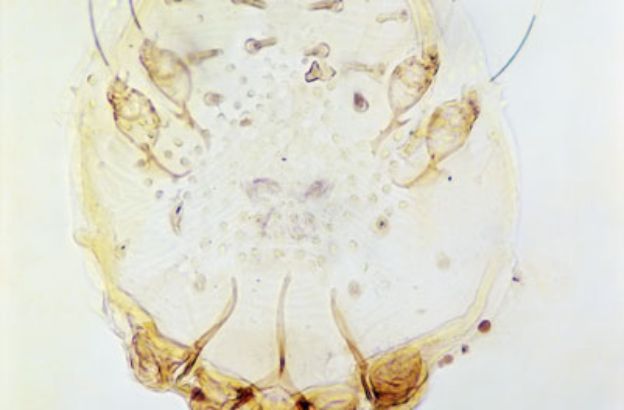

GENERE: Sarcoptes

Il minuscolo acaro della scabbia, invisibile a occhio nudo, è distribuito in tutto il mondo: l’unico limite evidente alla sua diffusione sembra essere la disidratazione, che non è in grado di contrastare a causa delle piccole dimensioni. Il corpo, interamente coperto da un tegumento di colore rossiccio, è ovale e non segmentato, e si può suddividere in 3 regioni: la prima reca 2 paia di appendici boccali, i cheliceri e i massillipedi, o pedipalpi; seguono la parte centrale, che reca 4 paia di zampe, e la terza regione, priva di appendici. Il primo paio di zampe, frequentemente più sviluppato, assolve funzioni tattili. Il cuore è assente o molto ridotto, e il sistema nervoso centrale è concentrato nella porzione anteriore del corpo; i principali organi di senso sono rappresentati da peli tattili. Le femmine scavano gallerie nello strato corneo della pelle di uccelli e mammiferi, compreso l’uomo, per cibarsi delle cellule cutanee. L’acaro della scabbia è responsabile della trasmissione della malattia da cui prende il nome, una dermatosi estremamente contagiosa che si trasmette mediante contatto con individui infetti o con indumenti contaminati dall’acaro.